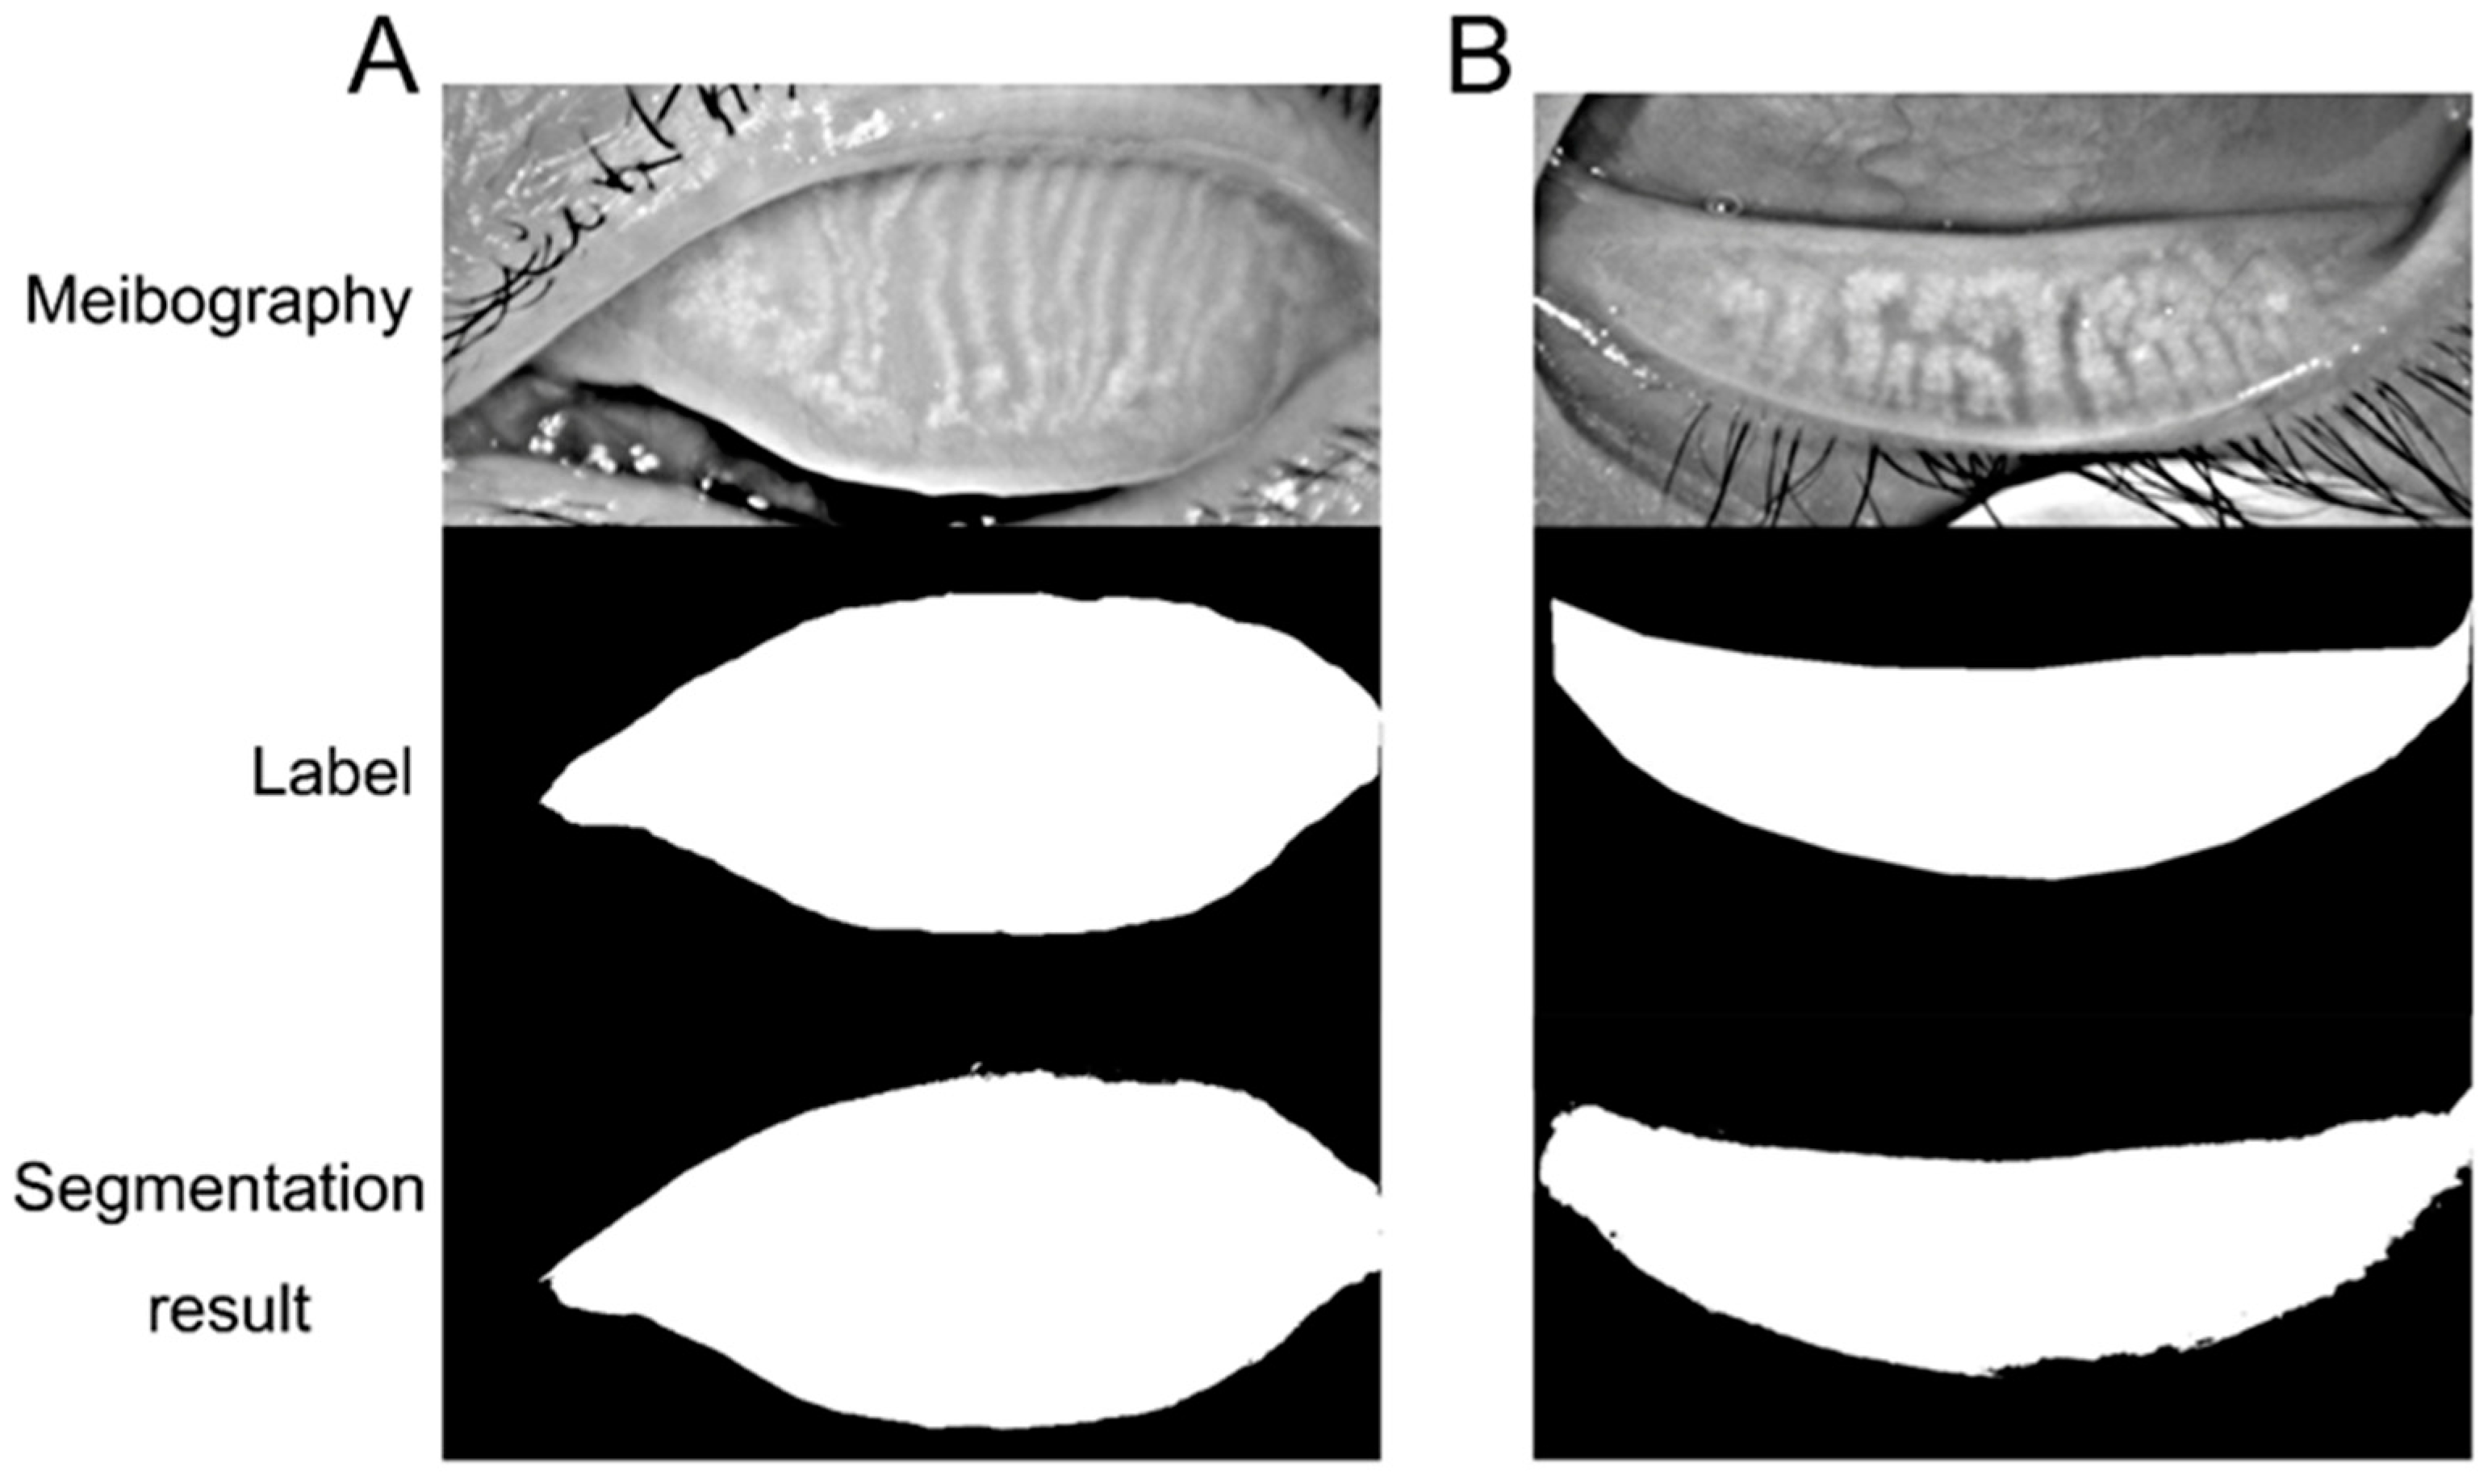

The tarsus region has a relatively definite shape. A VAE-GAN model was applied to extract and learn the shape feature. Then it could help the U-Net model to segment the tarsus region having a shape similar to the learned shape feature, as shown in

Figure 3. In the VAE-GAN, the encoder and decoder formed a stacked autoencoder, which encodes tarsus images (Ground Truth, GT / Real) manually labeled by human experts into a feature space represented by a hidden vector Z, which is passed to the decoder for randomly generating eyelid tarsus images (Fake). Finally, the prior knowledge of the shape of the tarsus region is embedded in the convolutional neural network by training the discriminator of the real tarsus and fake tarsus. Here, the generator (G) and discriminator (D) formed a Generative Adversarial Network (GAN), and they increased the sensitivity and discrimination of the discriminator to the specific shape of the tarsus region in the process of fighting each other.